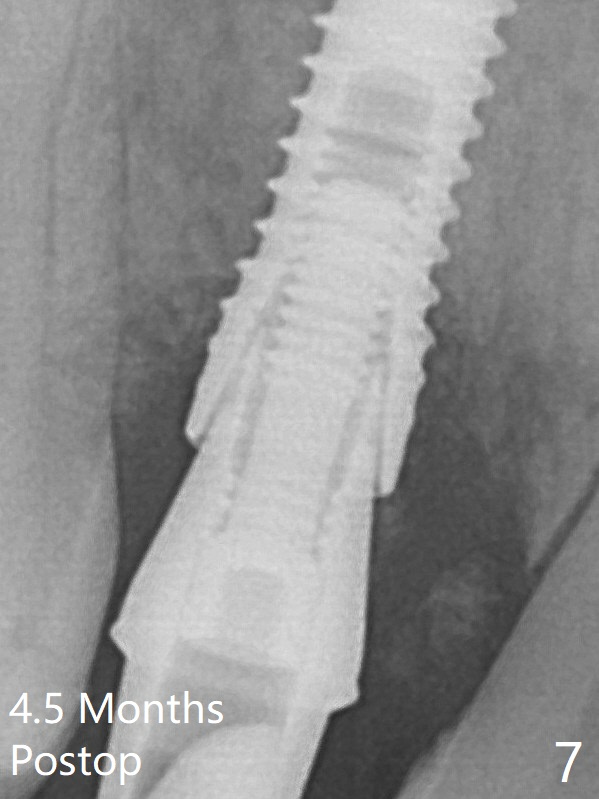

A final implant (3.8x15 mm) is placed with > 50 Ncm (Fig.4).  Before and after placement of a 4.5x5(3) mm abutment, Vera graft is placed in the remaining socket space (mainly buccal, Fig.5 *).  As routine, an immediate provisional is fabricated with occlusal clearance.  The bone graft appears to remain in place 4.5 months postop (Fig.7).  The bone density around the coronal portion of the implant increases 9 months postop (4 months post cementation, Fig.8).